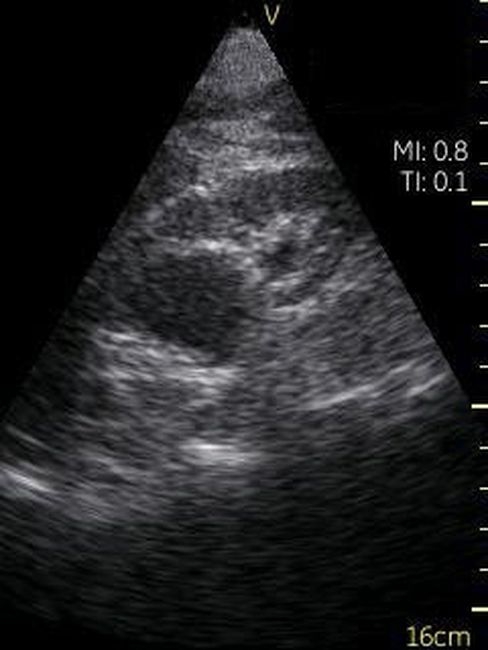

Визуализация Vscan:

· Черно-белый режим для визуализации анатомических структур в реальном времени.

· Поле зрения в черно-белом режиме: до 75 градусов с максимальной глубиной 25 см.

· Широкополосный фазированный датчик с частотой от 1,7 до 3,8 МГц.